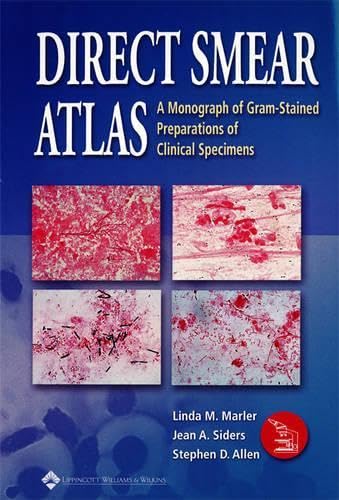

【感謝価格】 Direct Smear Specimens Clinical of Preparations Gram-Stained of Monograph A Atlas: 洋書

【感謝価格】 Direct Smear Specimens Clinical of Preparations Gram-Stained of Monograph A Atlas: 洋書

Direct Smear Atlas: A Monograph of Gram-Stained Preparations of Clinical Specimens,

Direct Smear Atlas: A Monograph of Gram-Stained Preparations of Clinical Specimens, Amazon.com: Andonstar HDMI Microscope Camera - True Digital HD Imaging at 1920x1080p Resolution- 300x Optical Zoom, (+4X Digital)- Brilliant : Electronics,